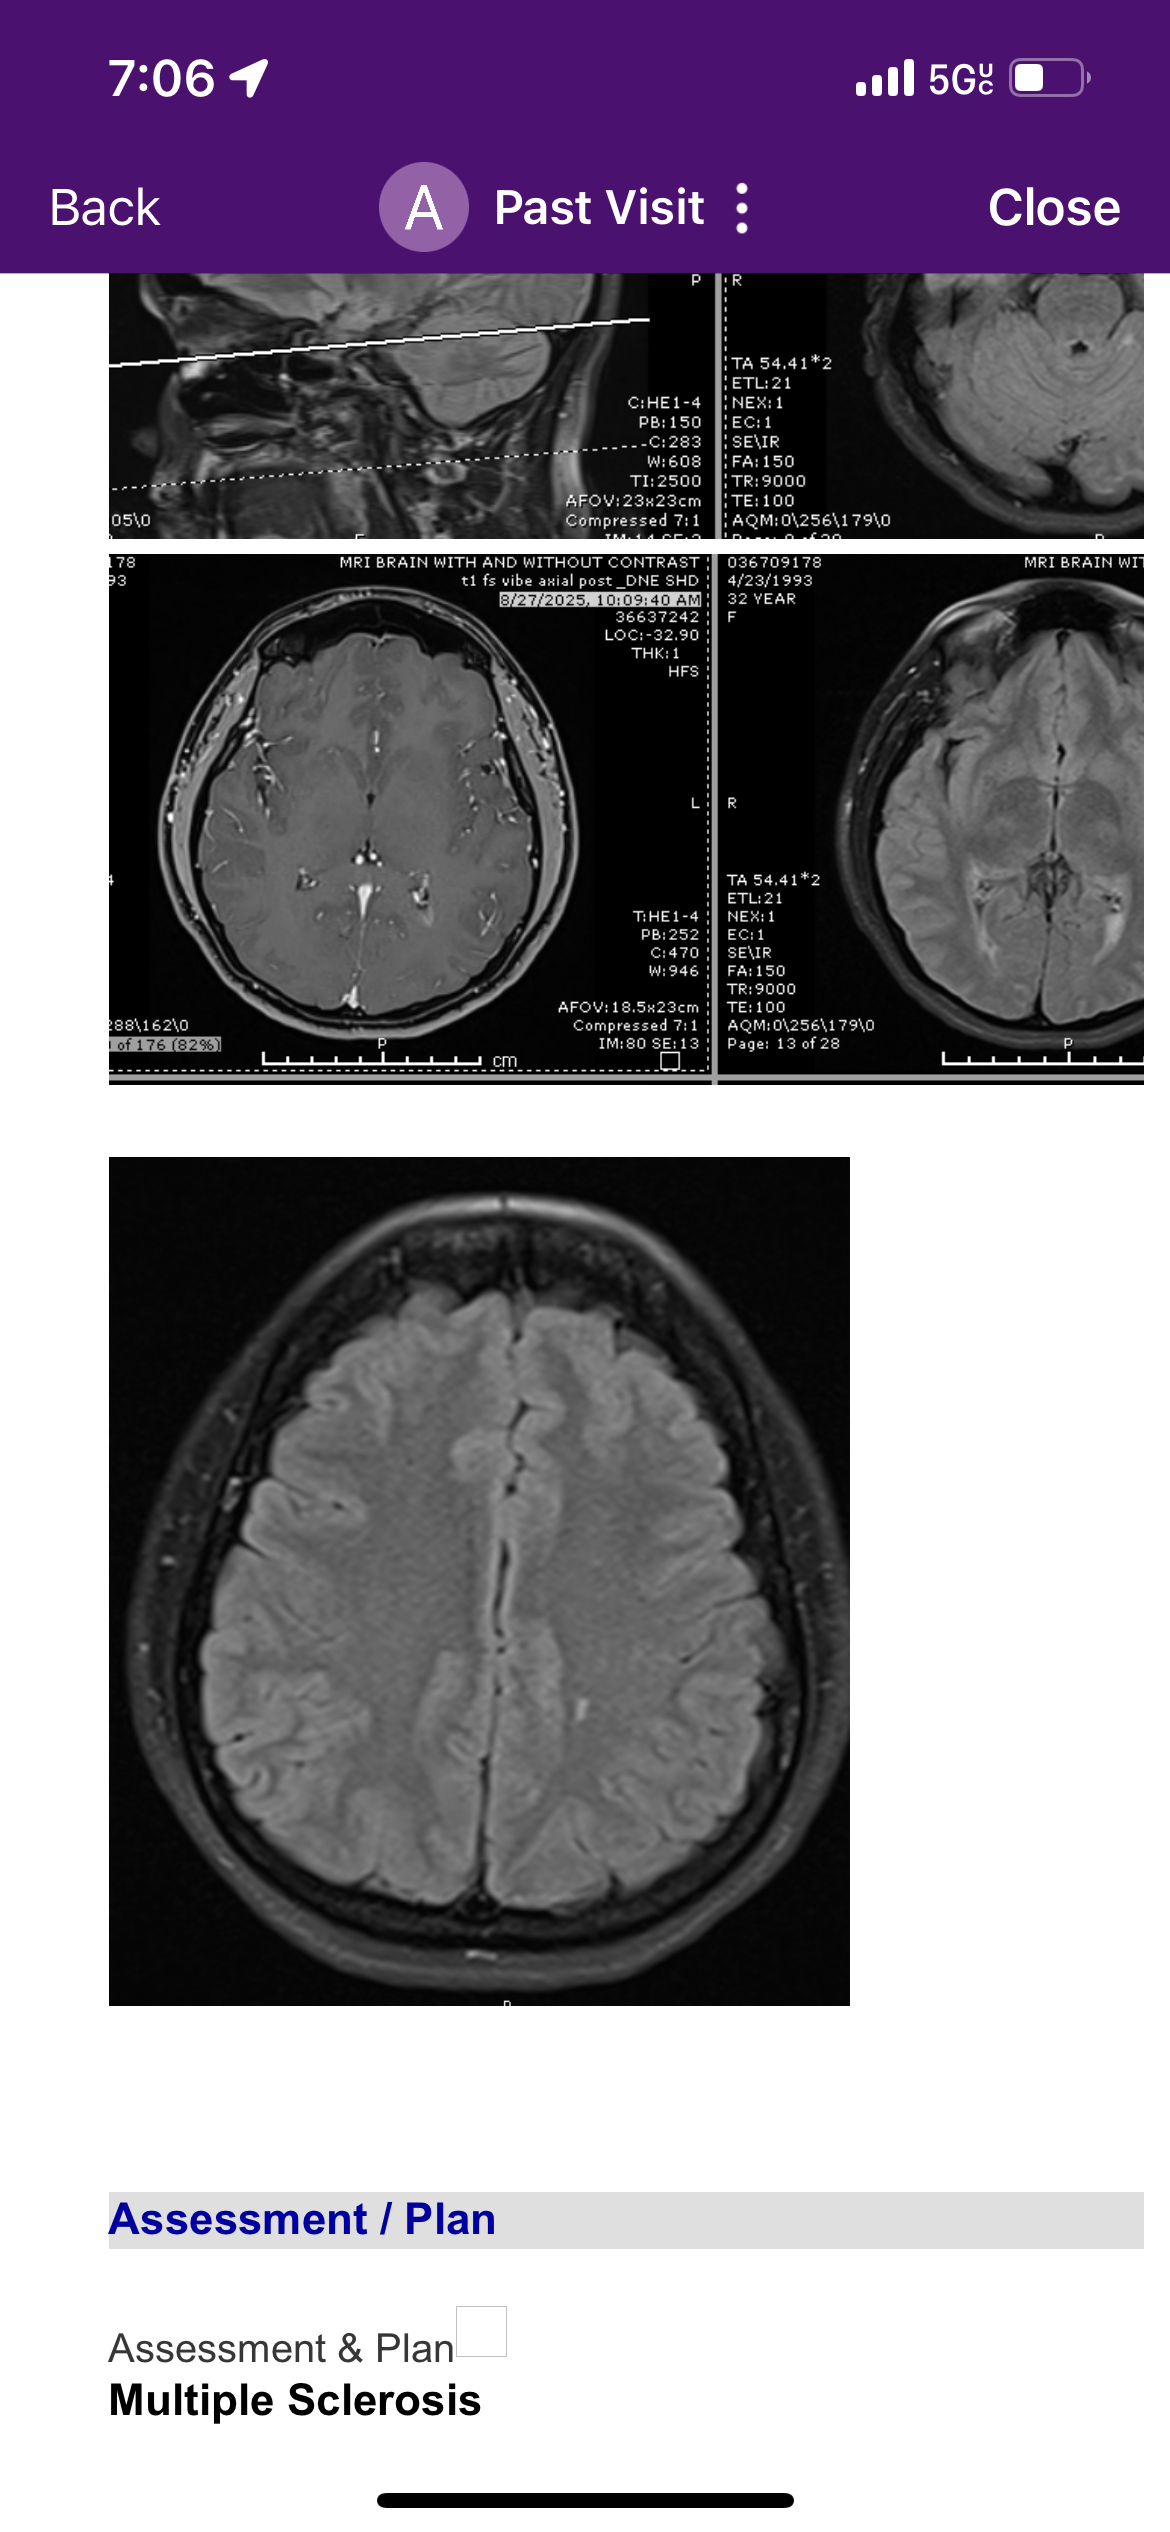

This summer I started experiencing frightening and debilitating symptoms— numbness through out my body, fatigue, vision problems, frequent headaches, neck & back pain— that doctor's believed was due to a tumor IN my neck spine disrupting my nerve's but through more recent MRI scans (pictures attached) after having taken steroids was found to be Multiple Sclerosis. (MS)

Este verano comencé a experimentar síntomas aterradores e incapacitantes: entumecimiento en todo el cuerpo, fatiga, problemas de visión, dolores de cabeza frecuentes, dolor de cuello y espalda. Los médicos creían que se debía a un tumor en la columna cervical que afectaba mis nervios, pero gracias a resonancias magnéticas más recientes (fotos adjuntas) realizadas después de tomar esteroides, se descubrió que en realidad se trata de Esclerosis Múltiple (EM).